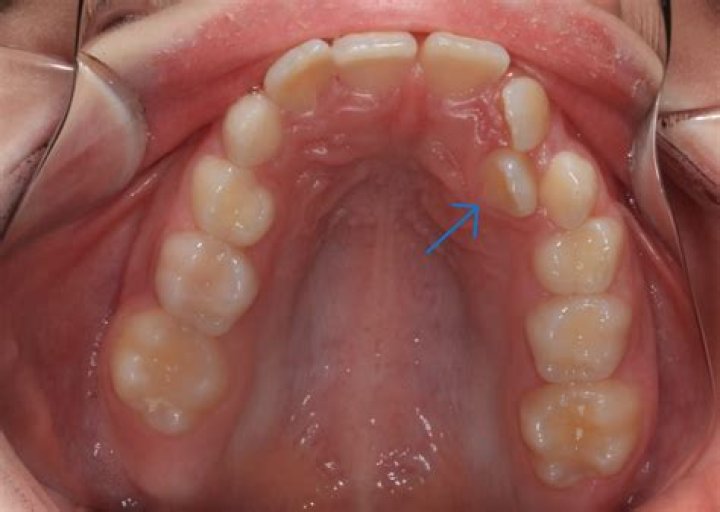

Hyperdontia: Extra teeth | supernumerary teeth

A mesiodens tooth is an extra (also known as supernumerary) tooth that grows in some children's mouths. This additional tooth most often appears between the top two front teeth and can disrupt your child's bite alignment and the growth of surrounding teeth.

What is the most common supernumerary tooth?

The conical which is a small peg-shaped tooth is the most common supernumerary found in the permanent dentition and it usually presents between the maxillary central incisors as a mesiodens.